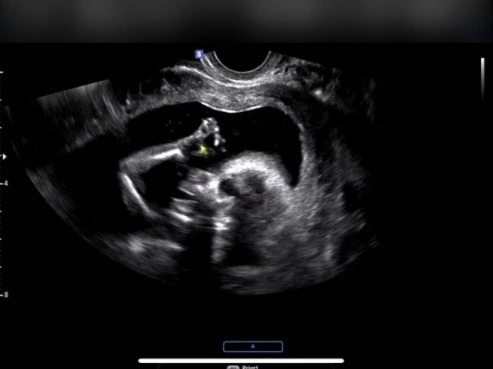

심장박동 정상, 양쪽 손 확인, 발 확인, 동공 확인, 양수 양 정상 등 정상/확인이라는 선생님의 말씀을 들으며 안도했다. 초음파를 통해 본 우리 아기는 손을 꼭 쥔 채 양수 속에서 둥글둥글 놀고 있었다.

아이가 엉덩이 쪽을 숨기고 잘 보여주지 않아 확실하진 않지만 딸일 확률 70%, 아들일 확률 30%라고 한다. 주변에서는 내가 임신하고 즐겨먹은 음식과 태몽으로 왠지 딸일 것 같다고 예측했다. 나도 12주 차 때 본 초음파에서 다리 사이에 뭔가(?)를 발견하지 못했기 때문에 딸이지 않을까 생각만 하고 있었다.